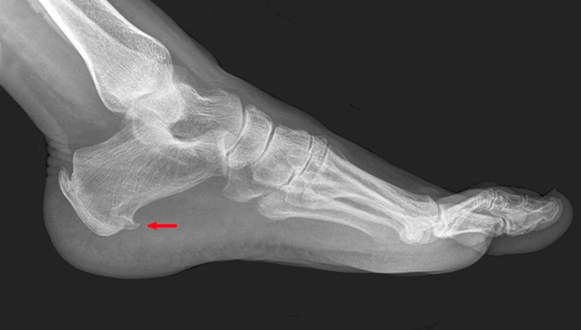

▶X光片:部分患者跟骨结节处有骨刺,骨刺的有无、大小与疼痛无直接的相关性;

跟骨结节可见骨刺(红色箭头)